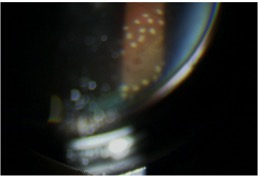

実際に当院で治療をした患者さんの写真です。網膜円孔の周囲をレーザーで凝固し、網膜剥離への移行を予防します。